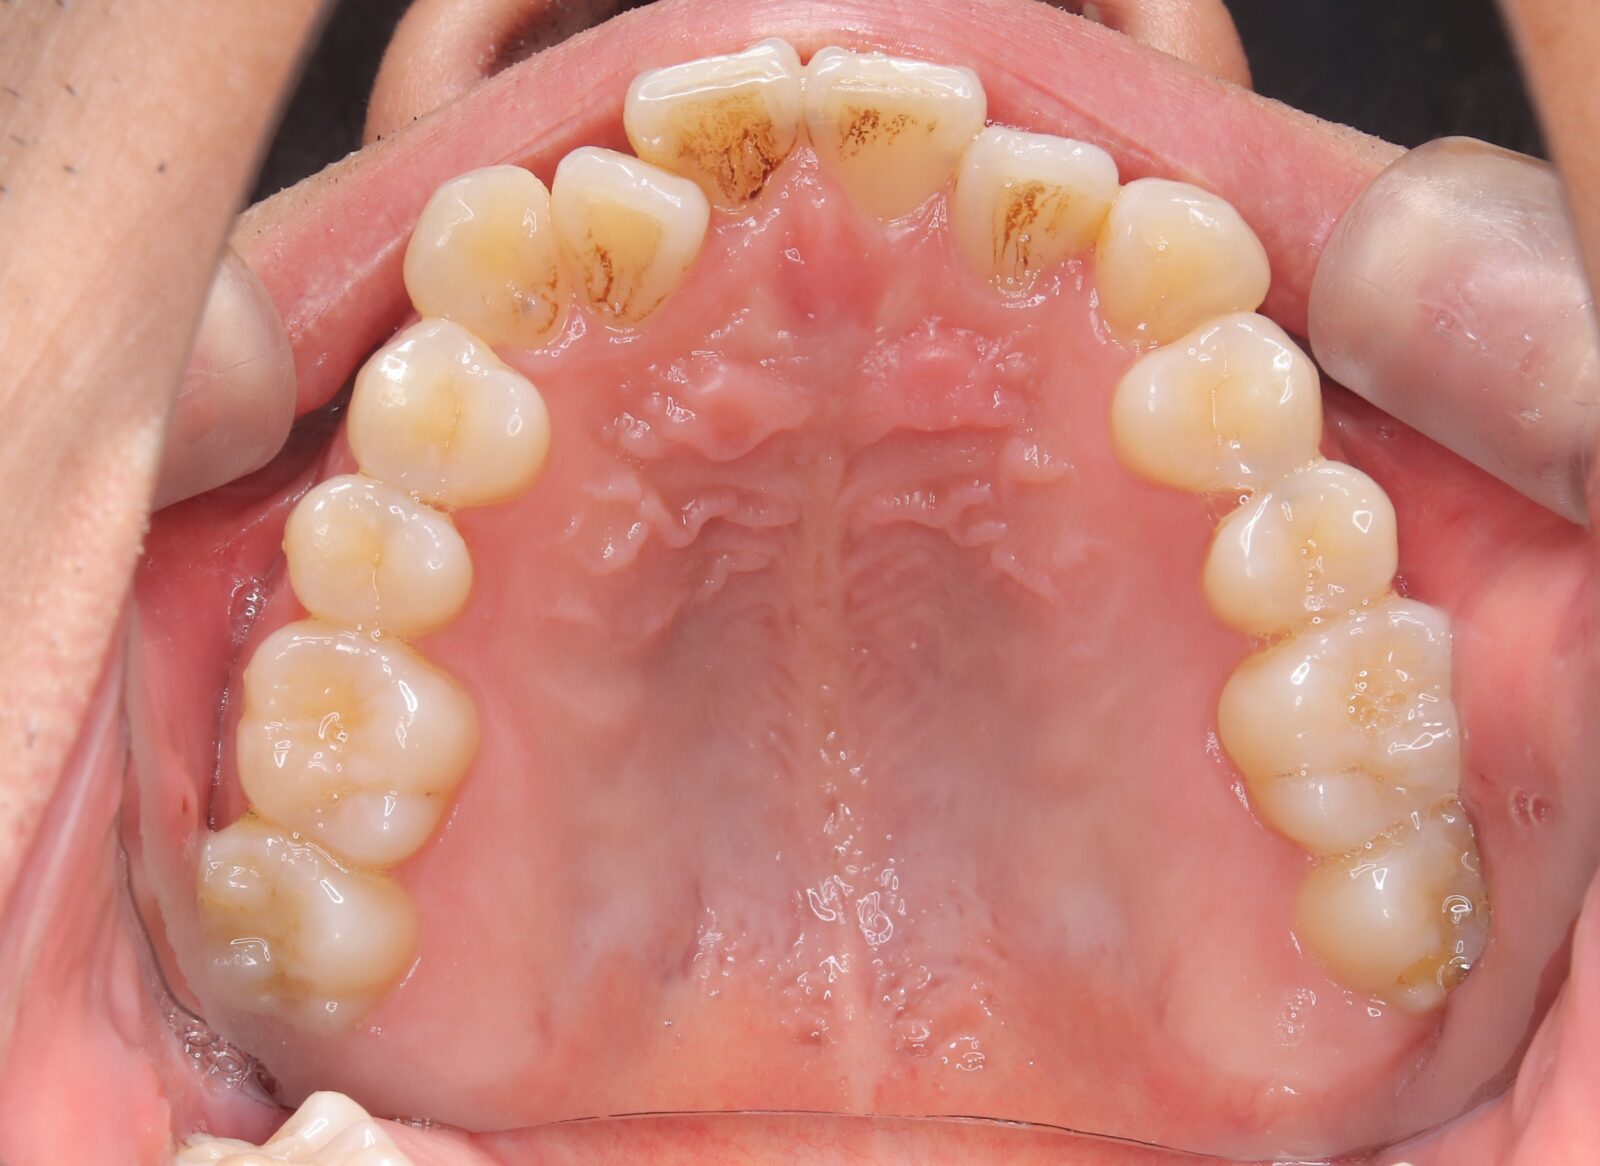

インビザライン(全体矯正)+ホワイトニングコースの症例

コンプレックスだった前歯の歪みと開咬(歯が閉じない状態)をインビザラインで美しく矯正。

・費用:935,000円(税込)

・治療期間:18ヶ月

・通院回数:18回

・32歳女性